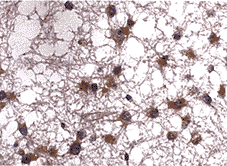

摘要 目的:探讨bcl-2和P 53在人脑胶质瘤中的表达及其与肿瘤分化的关系。方法:采用免疫组化SP法对35例人脑胶质瘤石蜡标本中bcl-2和P 53进行检测。结果:bcl-2和P 53蛋白在胶质瘤中的表达率分别为65.7%和37%。bcl-2阳性表达主要位于分化较好的星形细胞瘤;而P 53蛋白表达主要位于分化差的间变性星形细胞瘤和多形性胶质母细胞瘤。P 53阳性表达与肿瘤恶性度和病理分型均呈正相关。结论:在分化较高的肿瘤中以bcl-2表达为主,而在低分化肿瘤中以P 53表达为主,二者在调节胶质瘤的形成与分化方面可能起重要作用。

Abstract Objective:Toinvestigate bcl-2 and P 53 protein expression in human brain gliomas.Methods:Surgicalspecimens from 35 patients with human brain gliomas underwent a routine fixation,embedmentwith paraffin and immunohistochemical staining with a monoclonal antibody against P 53protein and a polyclonal antibody against bcl-2.Results:Bcl-2 expressionwas positive in 65.7% of gliomas,and a positive P 53 expression in 37% was shown.Mostastrocytoma was positive bcl-2 whereas most anaplastic astrocytoma and glioblastomamultiply was positive P 53.Conclusion:Most tumors of higherdifferentiation were showed positive bcl-2,whereas most tumors of lower differentiationwere in positive P 53,which may play an important role in regulation of tumorsdifferentiation.